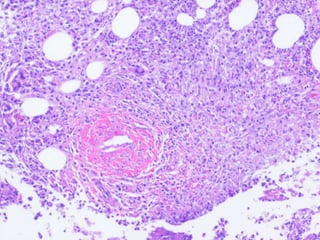

 Pulmonary disease: 70-75% isolates of

NTM

 Definition

 Usually adults

 Symptoms of cough, sputum production,

weight loss

 Two or more sputum isolates or one isolate

from, BAL, Bx, sterile site

 Distribution of isolates varies regionally

 MAC, rapid growers, M kansassi & M xenopi

 Pulmonary disease

 Common etiological agents

 M. avium complex(MAC)

 M. kansasii: one + sample diagnostic

 M. abscessus

 M. xenopi

 Lung biopsy

 Pulmonary disease:70-75% isolates of NTM  Definition  Usually adults  Symptoms of cough, sputum production, weight loss  Two or more sputum isolates or one isolate from, BAL, Bx, sterile site  Distribution of isolates varies regionally  MAC, rapid growers, M kansassi & M xenopi

• 16.

 Pulmonary disease Common etiological agents  M. avium complex(MAC)  M. kansasii: one + sample diagnostic  M. abscessus  M. xenopi